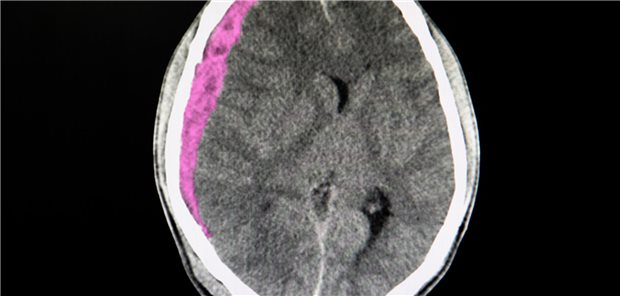

Patienten mit traumabedingter akuter subduraler Blutung bedürfen häufig der chirurgischen Entlastung. Welche Methode dabei zu bevorzugen ist, hat ein Team von Neurochirurgen analysiert.

Sollen Personen mit Vorhofflimmern nach einer intrakraniellen Blutung auf orale Antikoagulanzien verzichten? Keinesfalls, sagen chinesische Forscher. Andersfalls erhöht sich das Risiko für ischämische Ereignisse.